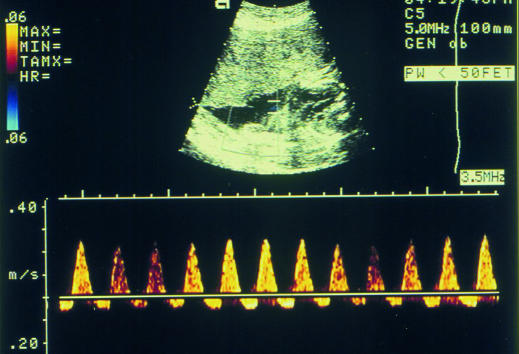

Figure 7.

Doppler measurement of umbilical arterial flow is used to test fetal wellbeing. This recording shows reversed end diastolic velocity waveform